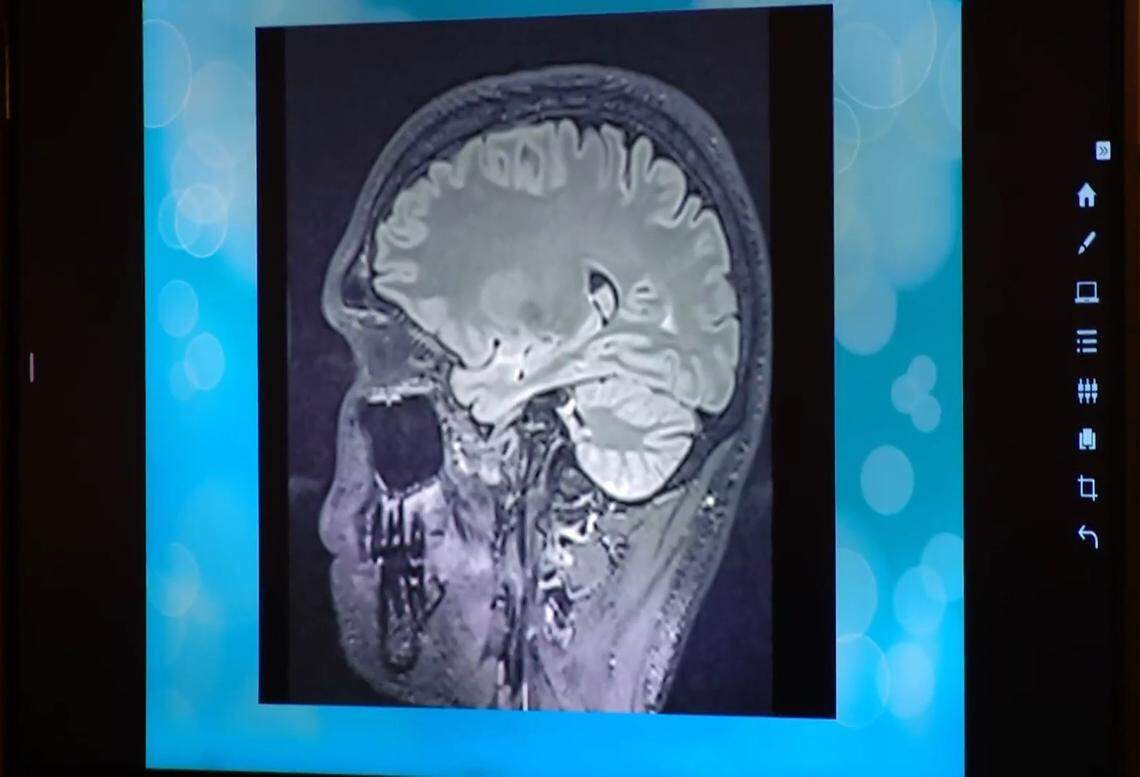

Jurors also heard from Dr. Jeffrey David Lewine, a PhD neuroscientist who evaluated Horner. The witness presented MRI and EEG scans of Horner’s brain, which he said showed significant abnormalities and general dysfunction in areas that deal with social cognition, emotional regulation of behavior, and short-term memory.

A scan of Tanner Horner’s brain was shown in court on Friday, April 24.

When Stainton asked why Horner wasn’t incapacitated by all the issues the scans revealed, Lewine testified that “this profile of abnormalities is still on the relatively mild side.”